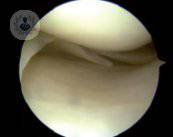

La rodilla es la articulación más afectada por la artrosis

La artrosis es una enfermedad degenerativa que afecta a las articulaciones, sobre todo afectando al desgaste de la rodilla. El Dr. Strauch, experto en Traumatología, habla de la patología y de su tratamiento.